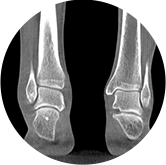

足踝

精準診斷